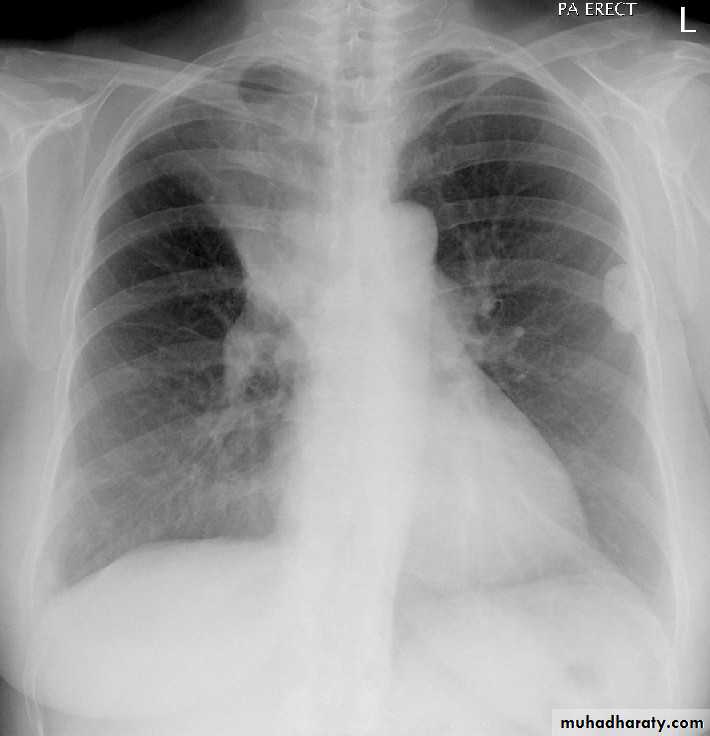

What is the main difference between 2 films ??? What is the shape of each one ??? A. B.

44.A.RT middle lobe consolidation

B.RT middle lobe collapse

Miliary TB